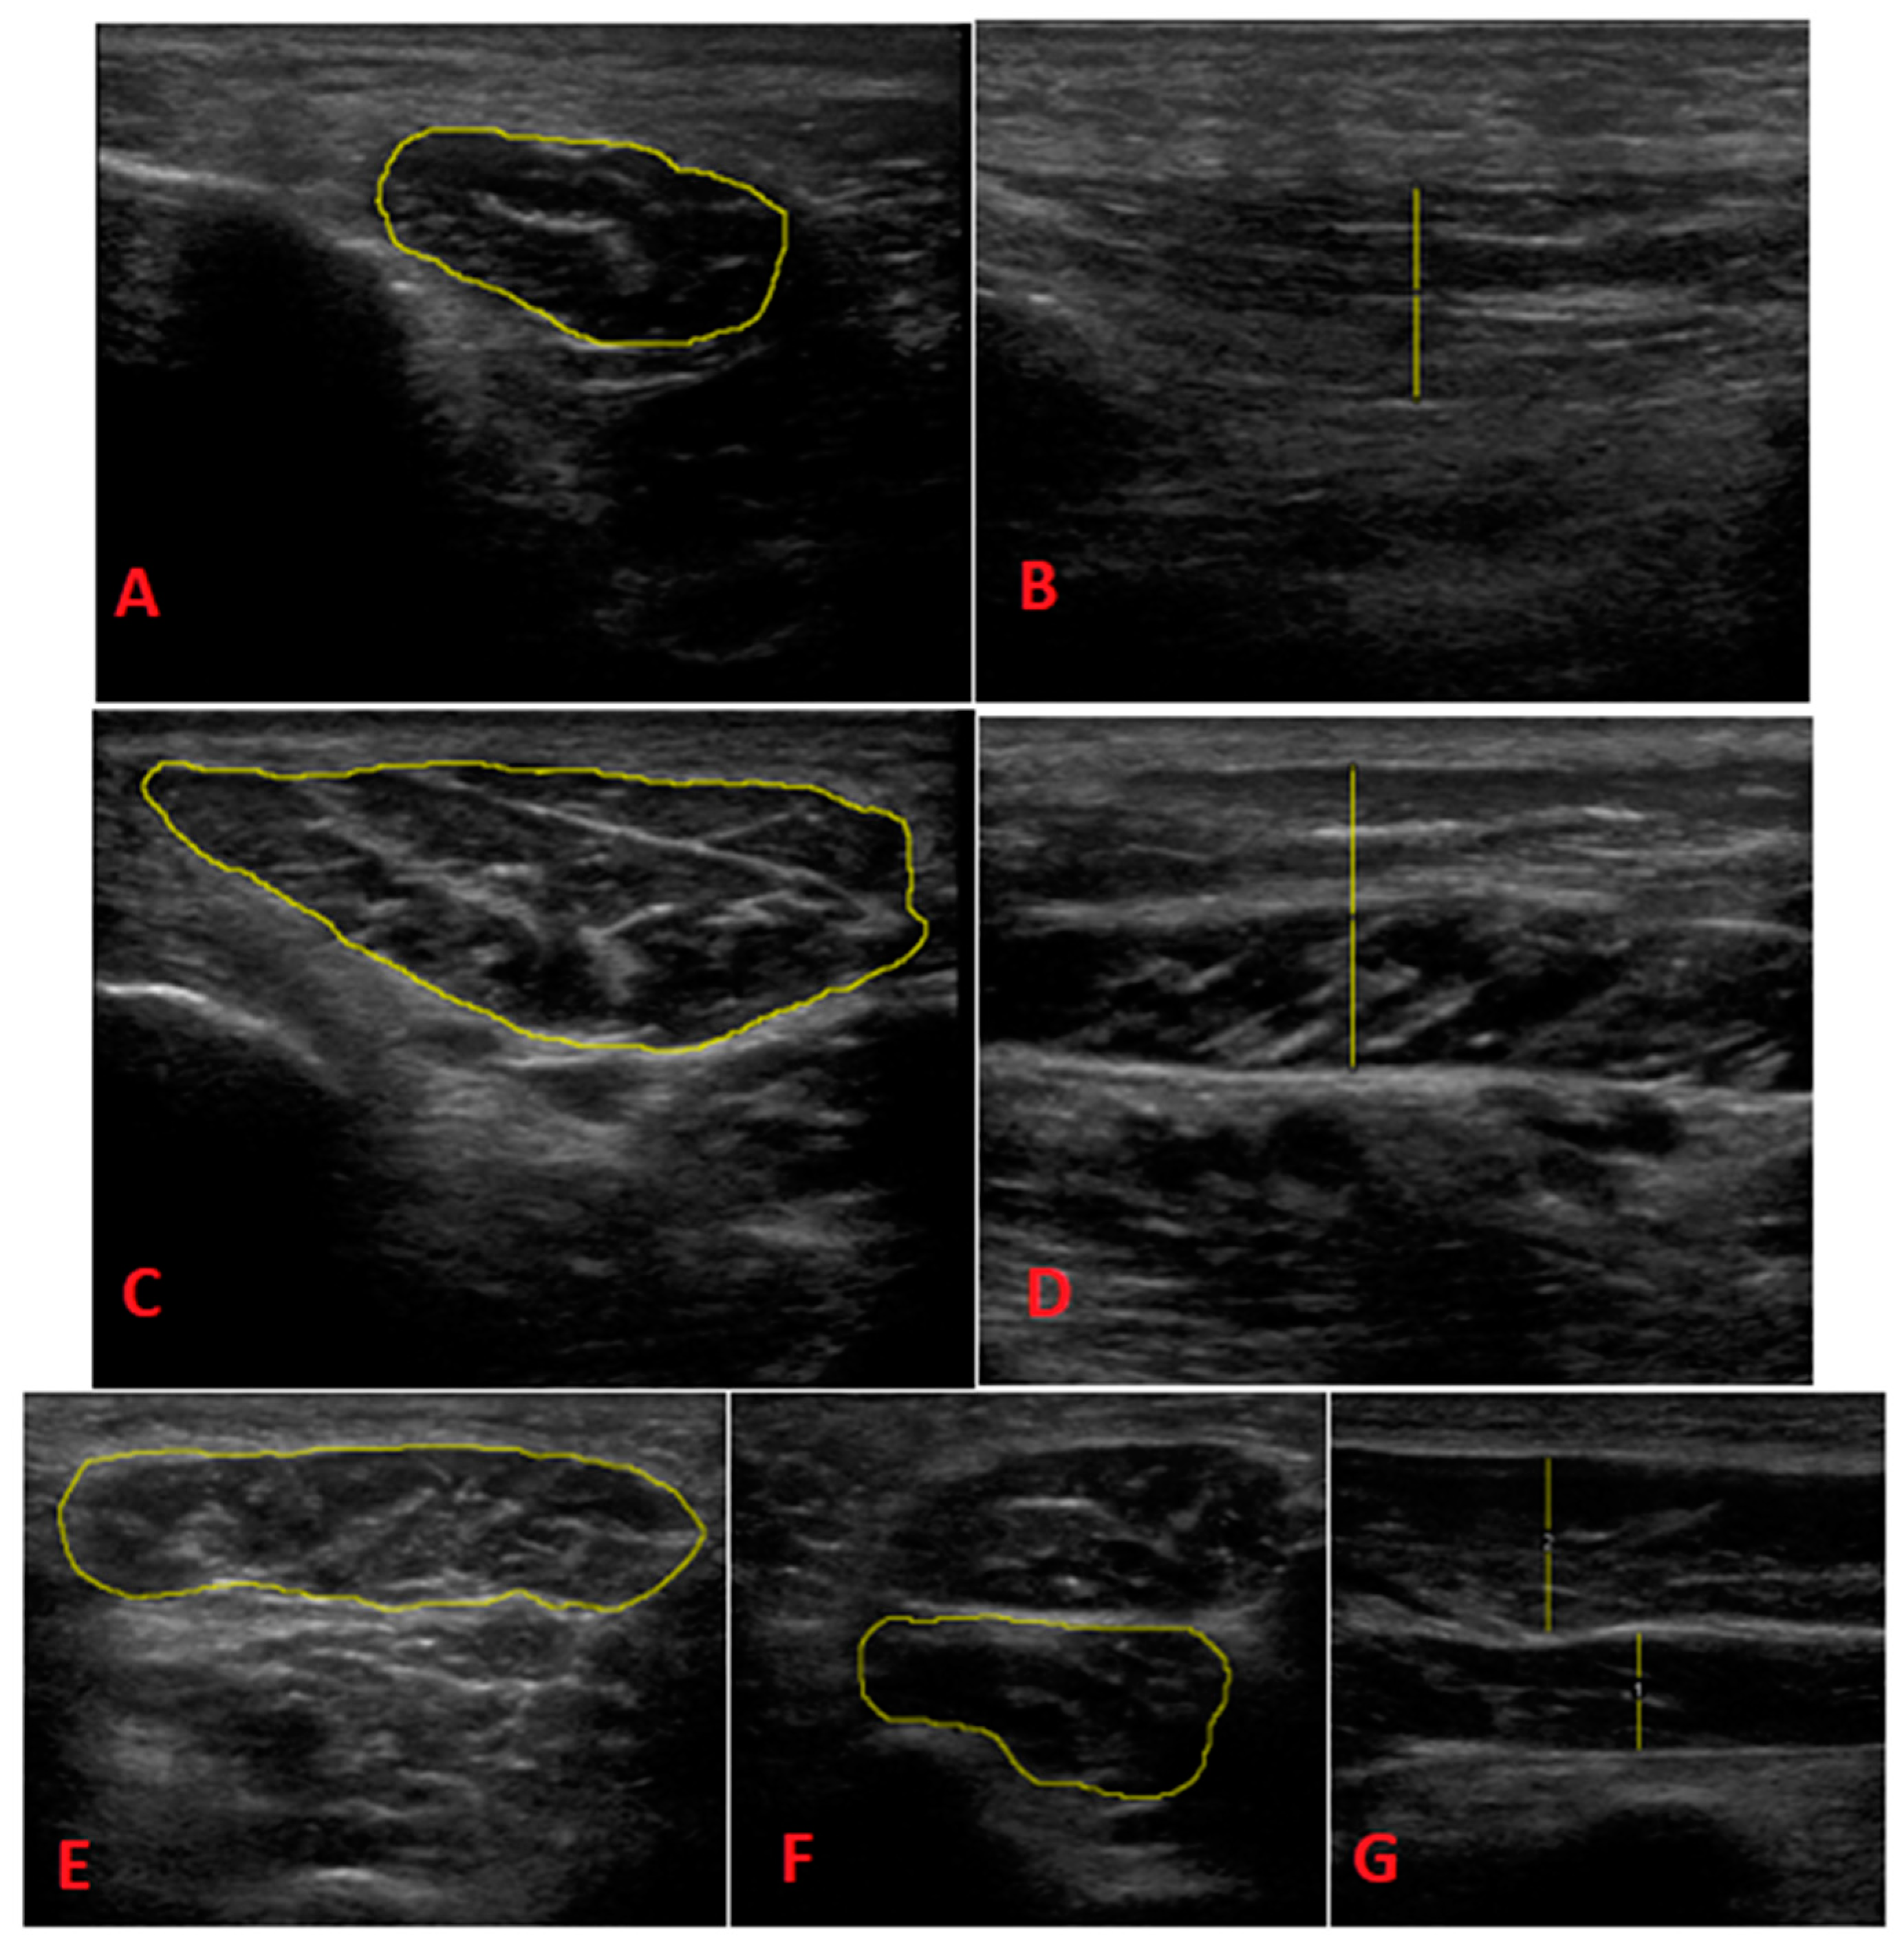

- FHB: Each patient was assessed in the prone decubitus position. We placed the probe longitudinally into the first MT (slightly oblique posterolateral direction). We then performed a proximal sweep to locate the thickest portion of the muscle belly, which was distal to the base of the first MT. The image was taken to measure the thickness.

- AbH: Each patient was assessed in the supine position with slight external rotation of the hip and slight knee flexion. We placed the probe into the medial tuberosity of the calcaneus toward the scaphoid tubercle. Normally, the area of greatest thickness is located 1–2 cm proximal to the scaphoid tubercle. A longitudinal image was taken to determine thickness and a transverse image was taken to determine CSA.

- AbDM: Each patient was assessed in the prone position. We located the insertion of the muscle in the lateral calcaneal tubercle and oriented the probe toward the tuberosity of the 5th MT. Normally, the area of greatest thickness is located near the calcaneocuboid joint, which was found before the tendon appeared. Longitudinal acquisition was performed to measure thickness and transverse acquisition was performed to determine CSA.

- QP: Each patient was assessed in the prone position. The quadratus plantaris was located deep in the flexor digitorum brevis. We then located the talus-calcaneus-scaphoid joint and used the longitudinal probe to align in the direction of the muscle fibers, looking for the area of greatest thickness in the muscle belly, which is usually found proximal to the spring ligament. We then measured the thickness in the longitudinal section and measured CSA in the transverse section.

- FDB: Each patient was assessed in prone position. We drew a line between the medial calcaneal tubercle and the third toe. We placed the probe in a longitudinal position relative to this line, which extended from the insertion in the calcaneus, and we performed distal sweeping until locating the area of greatest thickness in the muscle belly, before dividing it into 4 fascicles. The image was longitudinally taken to determine the thickness in the longitudinal section and transversely taken to determine the thickness in the ASC.

- Heel fat pad morphology: The longitudinal section was measured at the calcaneus level and in the area of greatest thickness of the heel fat pad [21]. Measurements were first taken without compression and then taken with compression. The distance between the skin and the plantar fascia (heel fat) was measured. The compressibility index was calculated by dividing the thickness in compression by the thickness without compression. The measurements of the heel fat thickness were also determined using Image J 2.0 software (National Institutes of Health, Bethesda, MD, USA), as was the intrinsic musculature determined via the foot assessment.